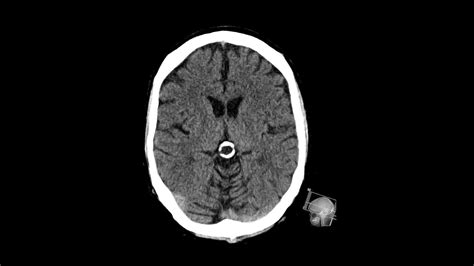

Diagnosing and Monitoring

In most instances, a Pineal Gland Cyst is discovered incidentally. Once identified, neuroradiologists evaluate the cyst using magnetic resonance imaging (MRI). The imaging helps determine the size, appearance, and whether the cyst is putting pressure on critical brain structures.

Feature Typical Findings

Size Most are smaller than 1 cm (often classified as "incidentaloma").

Appearance Smooth, thin-walled, and fluid-filled.

Growth Typically stable; they rarely grow or change over time.

Management Observation via follow-up MRI is the standard approach for small cysts.